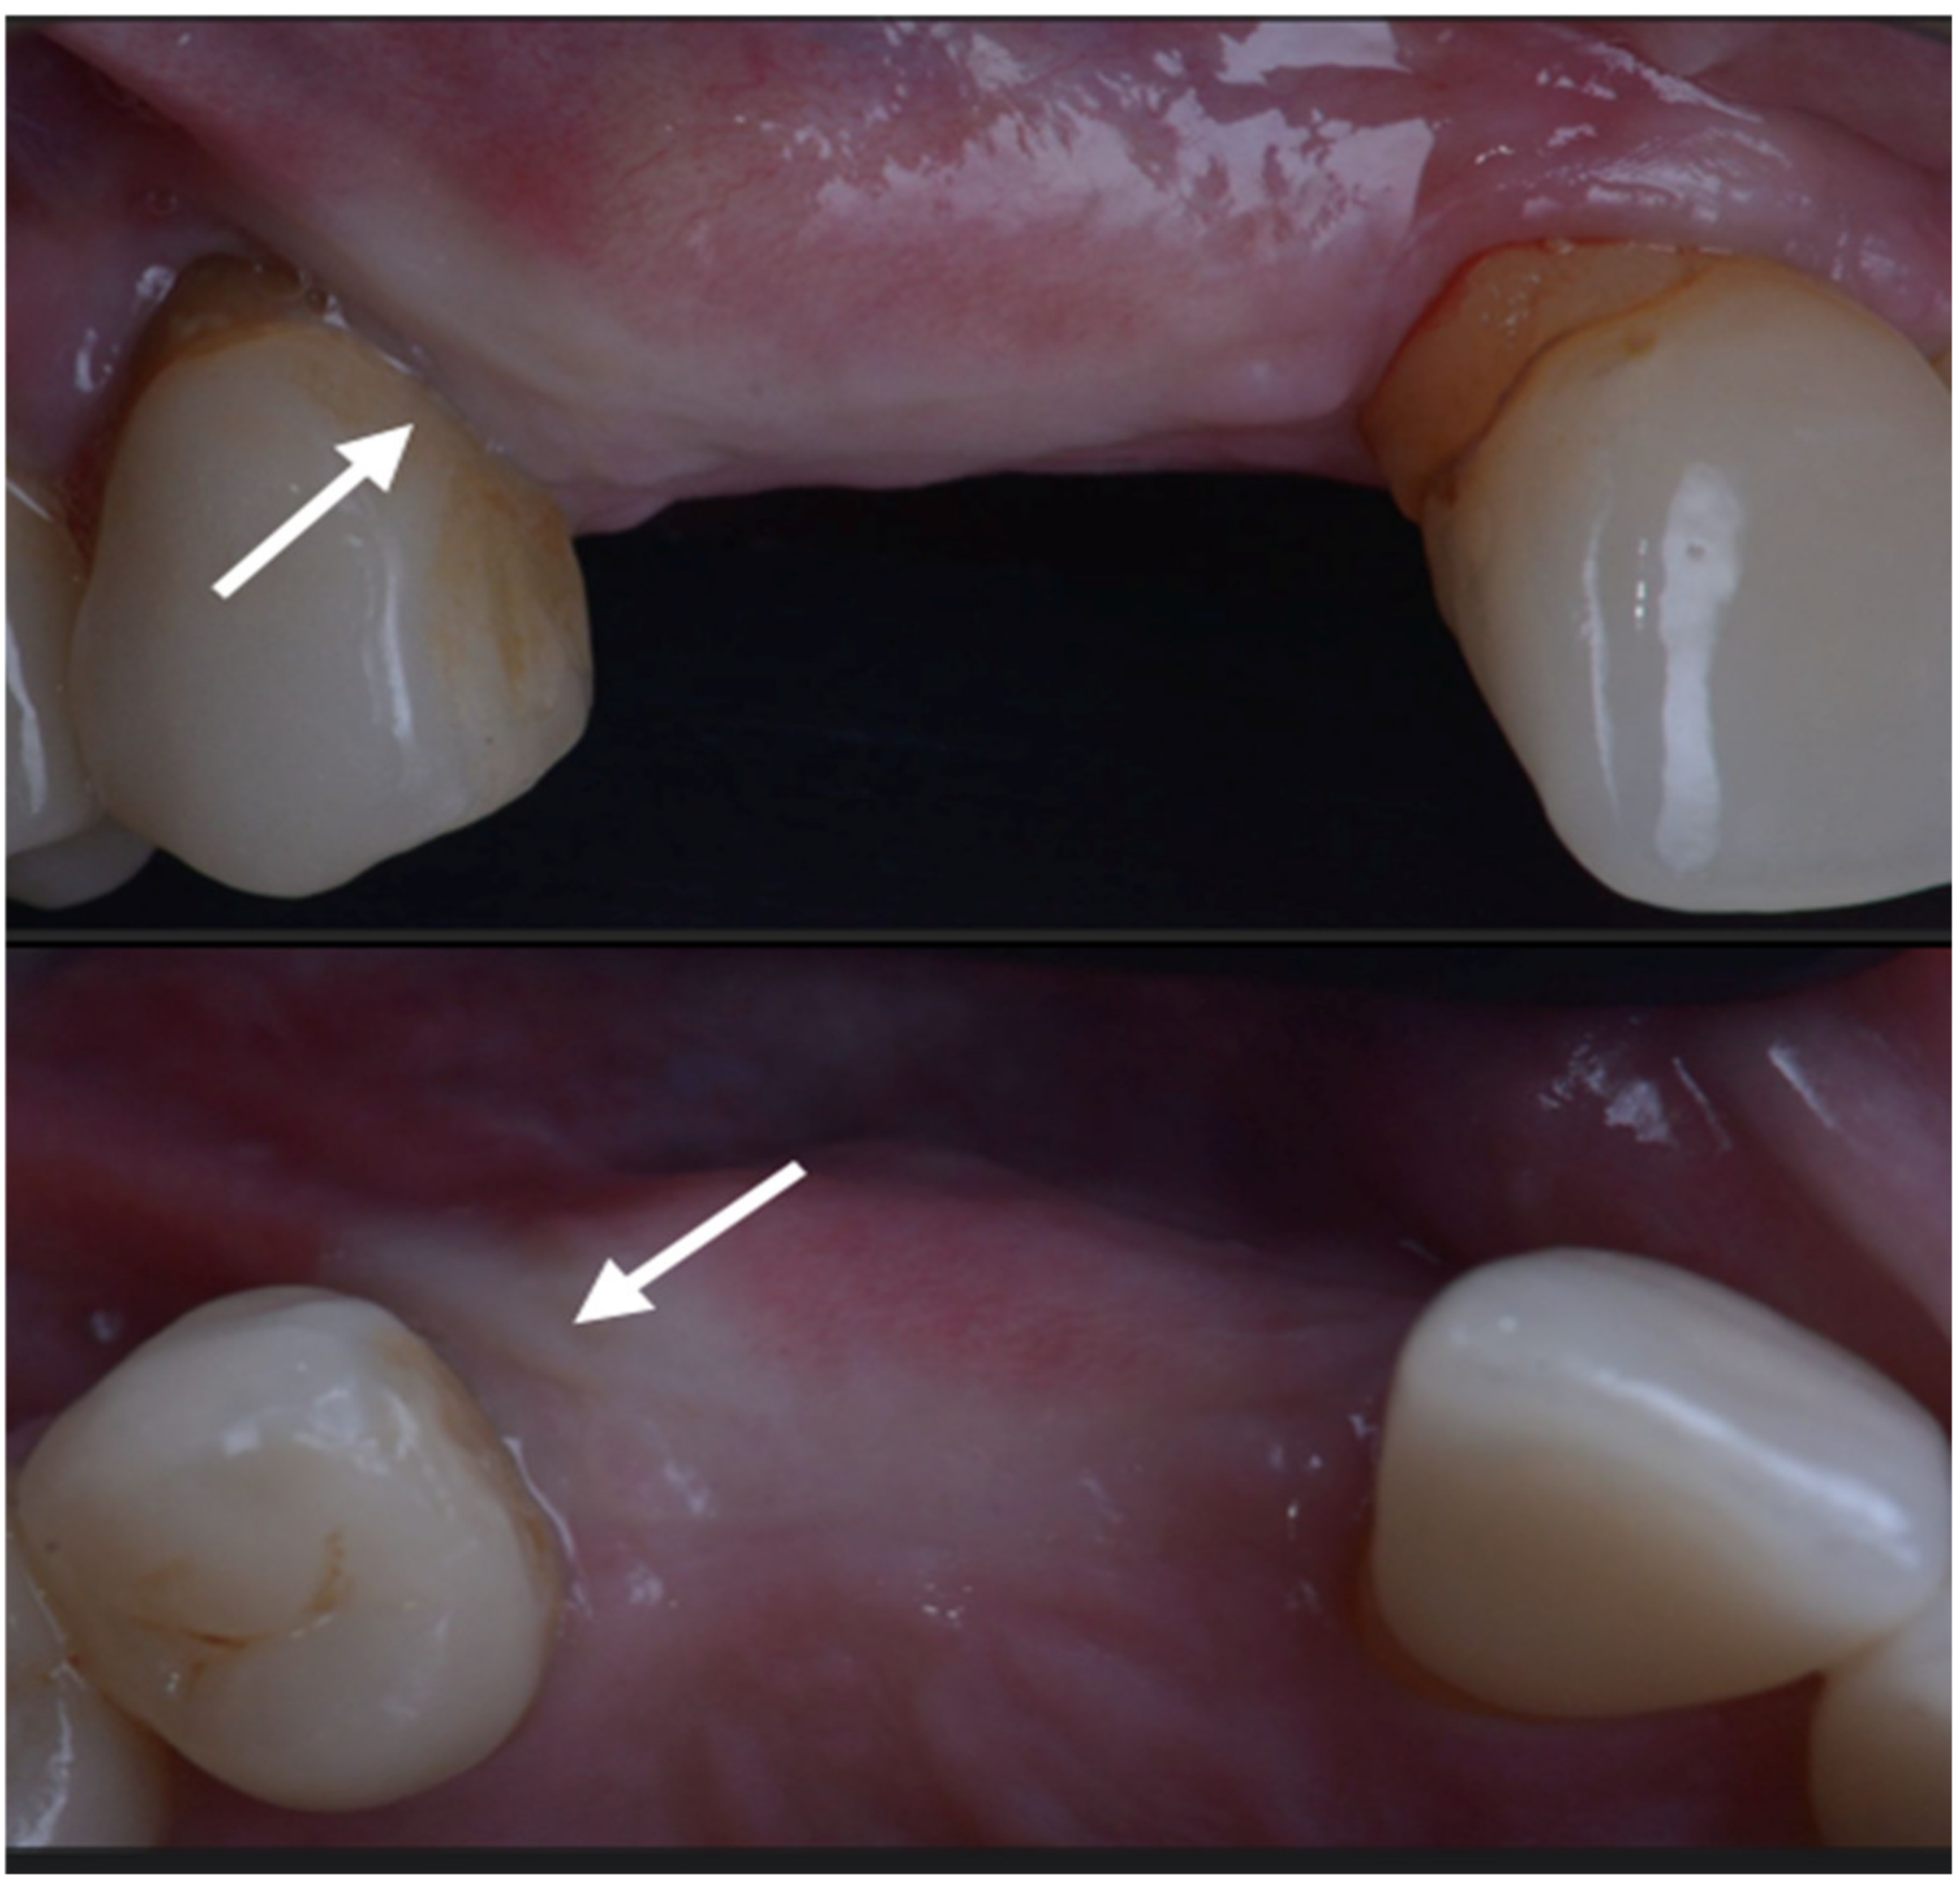

Six months after surgery the area looked really different from the clinical and radiographic point of view; soft tissue sits near the CEJ of the teeth and a buccal bulk is restored. (Figure 8 and Figure 9).

Figure 8.

At 6 months both the hard and soft tissue augmentation is evident.

The case has been followed for over three years and the stability of the soft and hard tissue are proof of the GTR effect of GBR. In this case, all parameters were restored in a still very young patient (Figure 12). The important aspect of the GTR effect is that teeth otherwise compromised at a young age are back in function with the support of both soft and hard tissue and all of this with only two surgical procedures. The presence of interdental-implant papilla is important to prevent food impaction and make the maintenance similar to that of the natural dentition. PPD at the time of recall were 2 mm to the distal of 15 and 2 mm to the mesial of 17; compared to the baseline, the gain of attachment was 4 mm for 15 and 5 mm for 17.

Figure 12.

Baseline and clinical and radiographic result 36 months after loading.